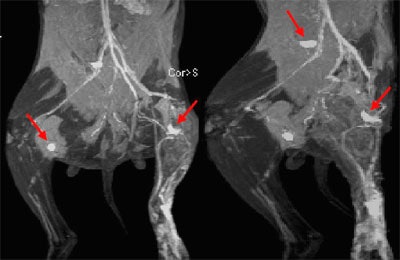

"The tumor invasion was visible as a signal void within the lymph nodes in the side ipsilateral to the VX-2 tumor," Herborn said. "These imaging findings were pretty well seen on the oblique views as well as the coronal views, and some of the structures like the thoracic duct could (also) be assessed." Even subtle tumor invasions, involving less than 25% of the node, could be visualized by rotating and postprocessing the images, he said.

| Above, coronal maximum intensity projection (MIP) image of interstitial MR lymphography in two rabbits with an implanted VX-2 tumor in left hindleg. Tumor invasion of left proximal popliteal lymph node can be assessed as circumscribed signal loss of tumor-bearing part (arrows) ipsilateral to the tumor in both animals, whereas contralateral nodes show homogeneous and bright enhancement. Note tumor invasion in enlarged iliac lymph node of the rabbit shown at right. Images and graphics courtesy of Dr. Christoph Herborn. |